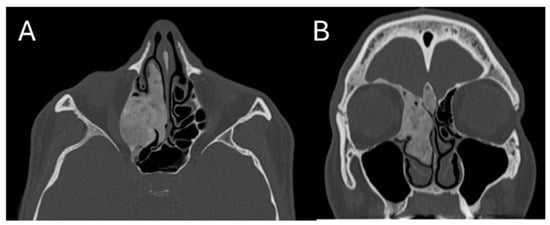

Under general anesthesia, an endoscopy of the right nasal cavity was performed, and the hypertrophy of the middle turbinate was appreciated, with a normotrophic overlying mucosa. A biopsy was attempted with Weil–Blakesley forceps, but due to the bone consistency of the lesion it was preferred to perform, through Piezo-Surgery [6] a fragmentation of the medium turbinate with a subsequent sampling of two operating samples of 15 × 25 mm and 10 × 10 mm, respectively (Figure 2).

Figure 2. Intra-operative fragmentation of the middle turbinate. The intraoperative phase is appreciated, during which the middle turbinate was biopsied using Piezo-surgery.